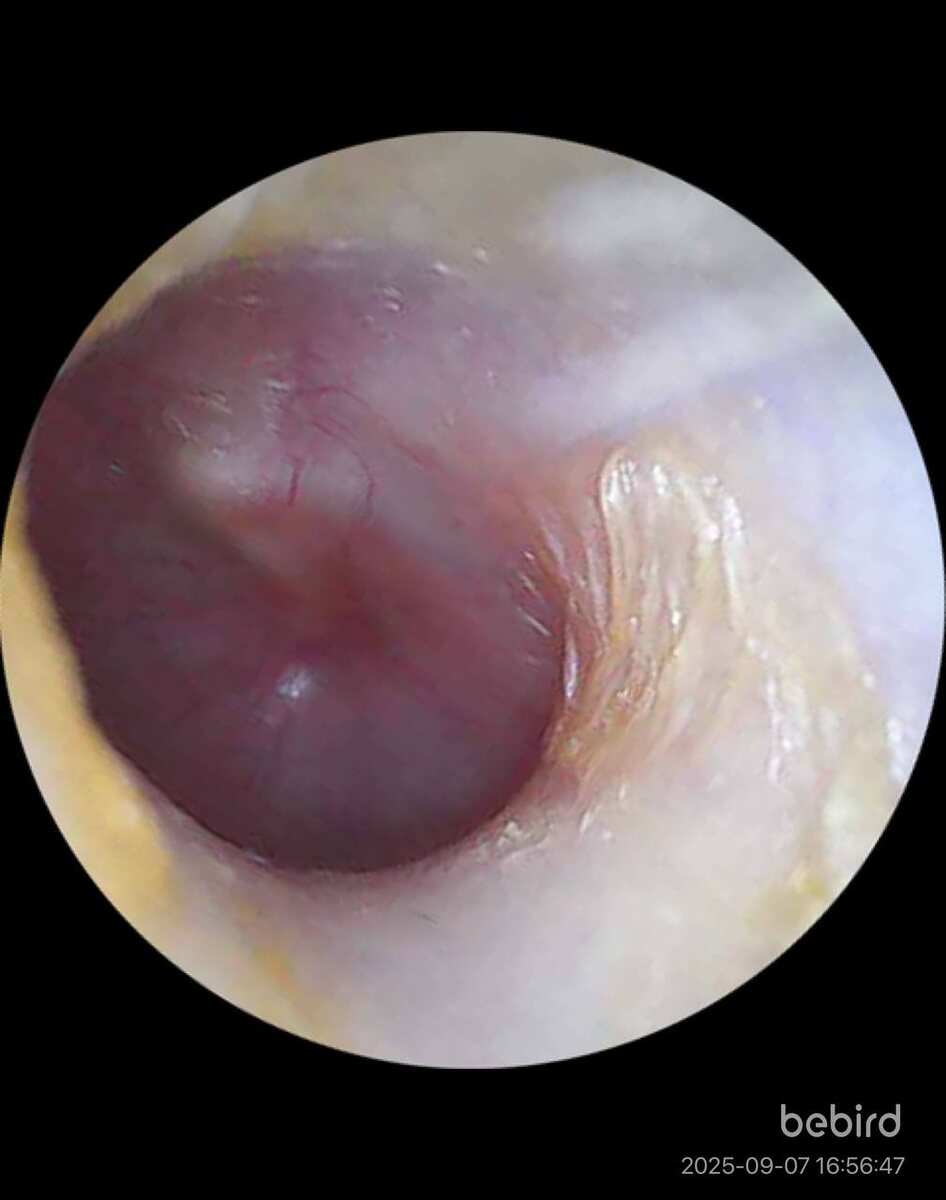

Фото 1. 📌Нормальная барабанная перепонка. Фото 2 Если жидкость сидит в ухе более 3-6 месяцев, она загустевает и постепенно превращается в рубцы. А рубец - это уже стойкое снижение слуха( Как только жидкость собралась в ухе, ребенок начинает плохо слышать. Это называется серозный или экссудативный средний отит. Возникает такой отит из-за ▪️ нарушения носового дыхания из-за аденоидов ▪️ хронического воспаления ▪️после острого среднего отита ▪️аллергии ▪️социальных факторов - пассивное курение, посещение ДДУ ▪️врожденных аномалий лицевого скелета - расщелина твердого и мягкого неба Не совсем глухой, конечно, но что-то недослышал, неверно услышал, отвлекся. В итоге, не понял, не верно ответил. Постепенно нарушается развитие речи и самоценность ребенка. 📌Экссудативный отит не лечат антибиотиками внутрь. Лечат причину. А жидкость из уха выходит сама в течении 3-6 месяцев. Если через 3-6 месяцев, жидкость в ухе сохраняется, ставят шунт в барабанную перепонку. Это такая катушка, ч

Вот так выглядит барабанная перепонка при жидкости в среднем ухе ребёнка из-за аденоидов. Фото 1.

Если жидкость сидит в ухе более 3-6 месяцев, она загустевает и постепенно превращается в рубцы. А рубец - это уже стойкое снижение слуха(

Как только жидкость собралась в ухе, ребенок начинает плохо слышать. Это называется серозный или экссудативный средний отит.